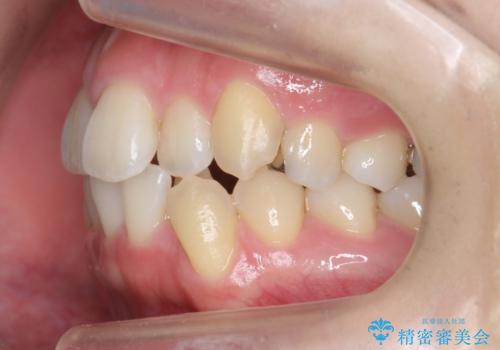

- 20代女性

- 矯正装置

- 審美装置

- 治療計画

- 前歯のがたつきと正中のずれを主訴に来院。

小臼歯を4本抜歯しています。

歯を抜いたことで、口元が下がって、横顔も理想的なラインになりました。